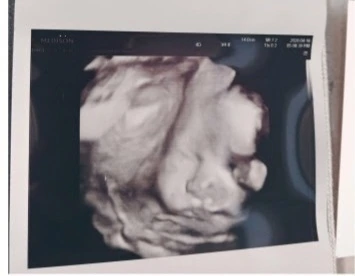

아이가 태어나기 전, 우리 부부는 아이 이름 짓기에 전력을 다했다. 요즘 유행하는 이름 TOP100부터, 좋아하는 글자들의 조합, 의미 있는 한자어들을 죄다 엑셀에 집어넣고 돌리고 또 돌려보았다. 우리는 무엇보다 아이의 '신체와 마음의 건강'이 우선이라 생각하고, 고심끝에 이름에 '건강하다'는 의미를 넣기로 했다. 우리의 아들은 뱃속에서 무탈하게 무럭무럭 자라 갔다. 모든 산전검사에서 이상이 없었다. 아이의 입체초음파 사진은 내가 사랑하는 남편을 꼭 닮아있었다. 앙 다문 입술과 오뚝한 코가 특히. 우리는 아이에 대한 기대감으로 하루하루를 쌓아나갔다.

첫 입체초음파 사진. 알아보실 수 있으려나요?